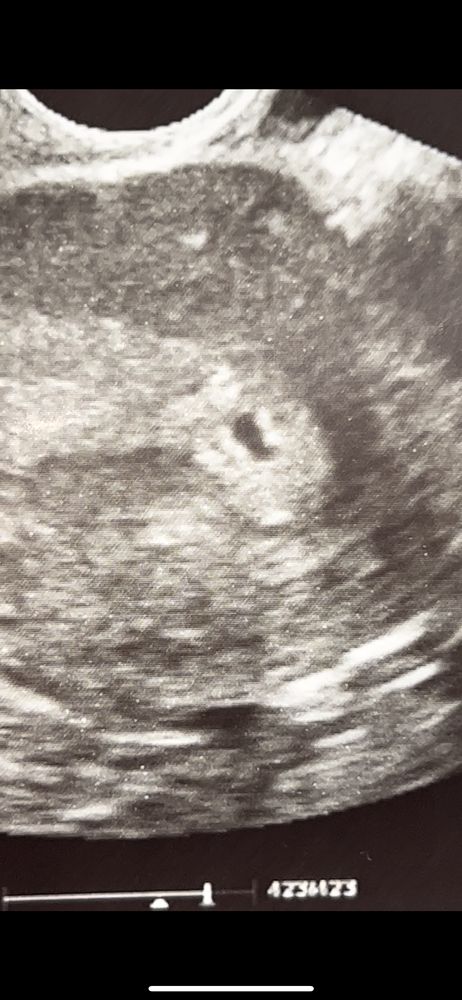

Добрый вечер) подскажите пожалуйста, вчера сделала УЗИ, беременность малого срока. И разглядываю вот картинку и не пойму что это такое. Плодное яйцо это понятно, а вот что за две точки белые? Это просто неровность же?

подскажите пожалуйста, кто разбирается